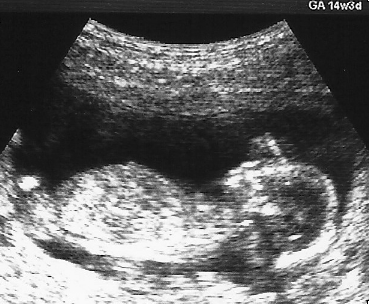

胎児超音波検査 (産婦人科領域のエコー) について

超音波検査は生体への侵襲の低さが最大の利点であり,母児に対して行う画像診断法として 広く普及している検査法です。